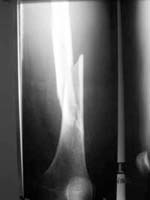

| Abb.: Präpoperativ I |

Abb.: Präpoperativ II |

Gleich danach füllt sie die Röntgenanforderung aus. Da Oberschenkelfrakturen oft mit Schenkelhalsfrakturen oder Kondylenfrakturen einhergehen, schreibt sie:

Als sie auf die Röntgen-Ergebnisse wartet, führt sie bei Stefan eine Abdomen-Sonographie durch, um Verletzungen der Bauchorgane nicht zu übersehen. Sie findet aber keine Auffälligkeiten. Das Blutbild und die Röntgenbilder sind jetzt da. Nach dem ersten Blick auf die Bilder ist Dr. Noll klar, dass sie Stefan operieren wird. Sie ruft den Oberarzt hinzu, um das OP-Verfahren abzuklären.